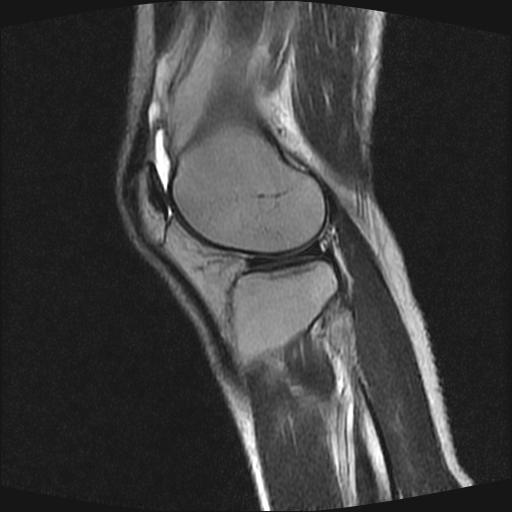

40岁男性,右膝关节外伤,x光平片示,髁间隆突撕脱骨折。

前交叉韧带撕裂,关节腔积液.

半月板1-2级损伤   前交叉韧带撕裂伤   关节腔少量积液  诸骨未见新鲜外伤性改变

前交叉韧带撕裂,关节腔积液,支持!

内侧副韧带撕裂及关节腔积液是肯定的,但是前交叉撕裂确定吗?会不会有容积效应的因素,因为前一张前交叉显示清楚,连续性良好,且较光滑。请问楼主有关节镜支持吗?我们医院也经常有这样的患者,但苦于没有关节镜,而无法对照、证实(除非完全断裂),出现了不同的诊断结果只能毫无意义的争论。

除了关节积液外并无韧带撕裂,acl胫侧附着点有2束,正常情况下脂肪信号。此病例应加做压脂像以便观察是否有骨损伤。